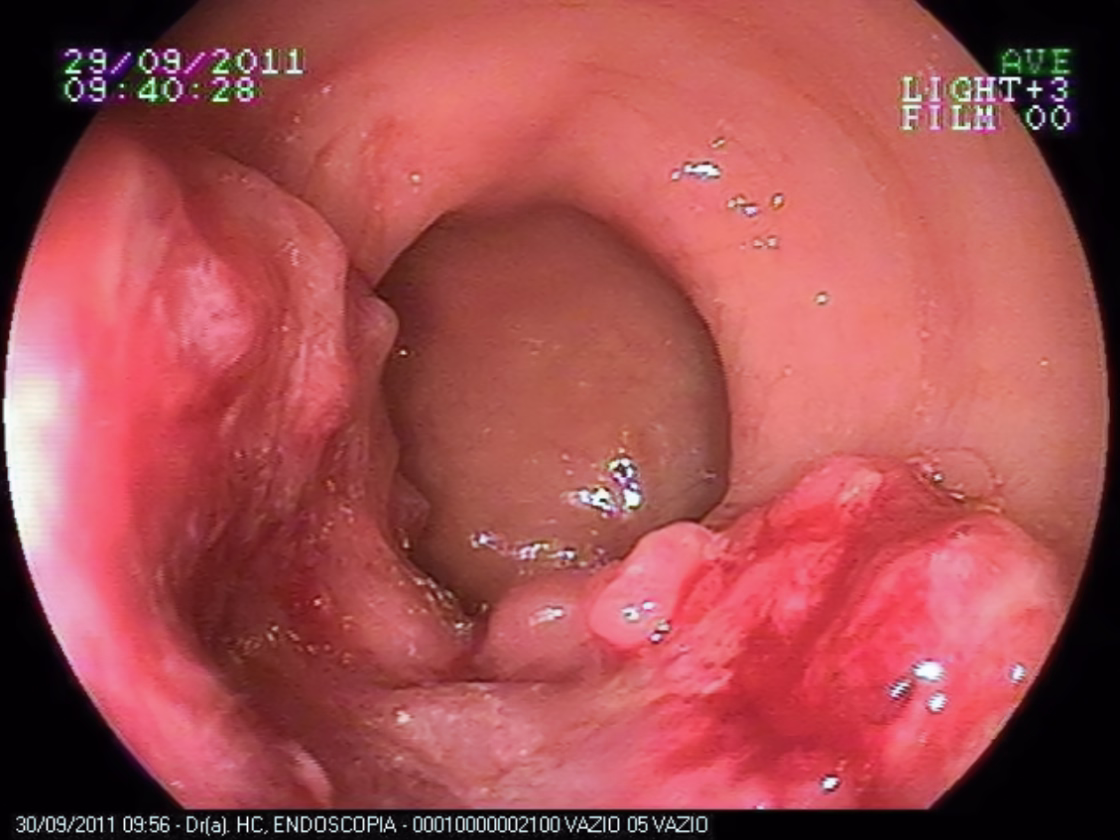

Figura ilustrando um exame de colonoscopia que diagnosticou câncer do intestino grosso

Como se Faz o Diagnóstico de Câncer do Intestino Grosso?

A colonoscopia é o melhor método para estabelecer o diagnóstico. Este exame permite visualizar o tumor e obter biópsia para confirmar o diagnóstico.